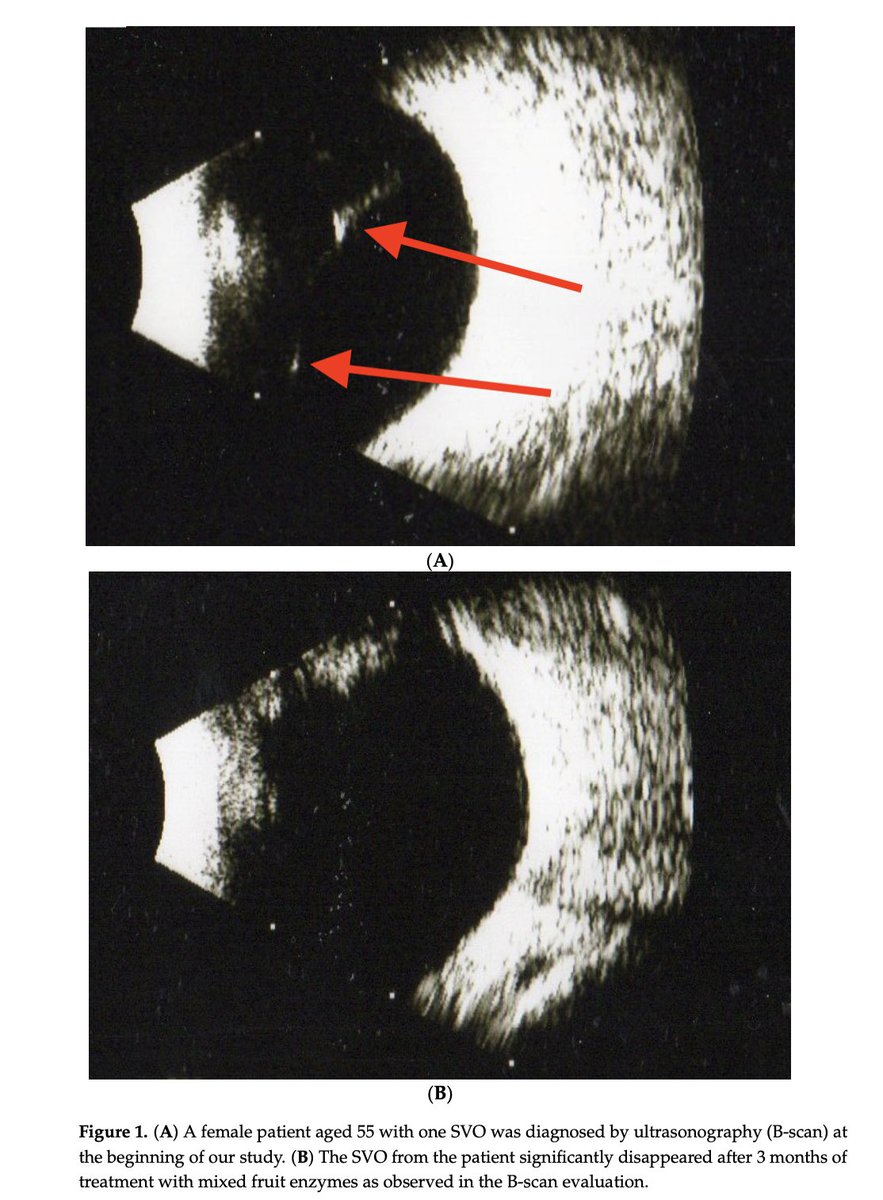

Eye floaters eliminated with fruit enzymes.

Literally dissolves the floaters away within months.

Eye floaters disappear within 3 months of taking fruit enzymes. The enzymes contained in pineapple, papaya and fig: ⬩190 mg bromelain ⬩95 mg papain ⬩95 mg ficin Literally dissolve the floaters away.